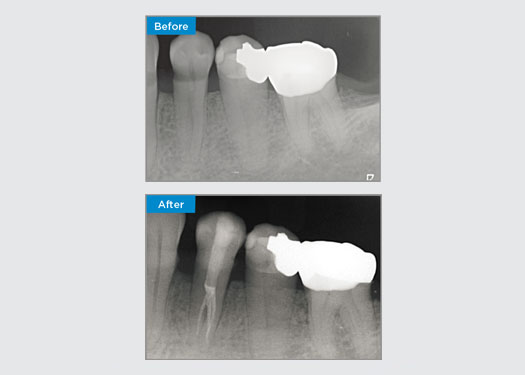

El paciente presentaba pulpitis irreversible en el diente 46. En la radiografía preoperatoria, el diente 46 se presenta con una raíz distal adicional (morfología del diente Radix Entromolaris). Los datos del CBCT confirman la presencia de raíz DL con curvatura radicular grave. Una selección cuidadosa de la lima es fundamental para esta raíz DB.

Dr. Jack Lin, endodoncista, Sídney, Nueva Gales del Sur, Australia

En esta situación, la preservación de la estructura del diente y la raíz es esencial para reducir el riesgo de desplazamiento, transporte, compresión, perforación y fractura de la raíz. La selección de casos, el diagnóstico y la planificación previa al tratamiento son muy importantes. Es fundamental la selección de limas de endodoncia con flexibilidad, eficiencia y respeto por la anatomía natural de la raíz.